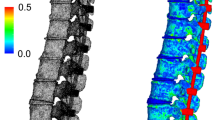

A new test method for the simulation of everyday activities such as climbing stairs, tying shoes and lifting heavy weights (up to 20 kg) could be developed and validated. In the dynamic loading protocol of this test method, axial loads that were calculated from in vivo intradiscal pressure measurements were applied to the fused specimens. Additionally, combined motions of up to ± 1° in flexion–extension and lateral bending were created in order to provoke circumferential subsidence effects. This test method was successfully used to provoke typical subsidence schemes that are reported clinically (Fig. 5). Macroscopically, signs of subsidence could be seen in both groups with the different endplate geometries. Implants with round endplates subsided remarkably deeper into the adjacent vertebra than their lateral endplate implant counterparts, which primarily began subsiding when simulating lifting heavy weights. This difference presumably derives from the additional apophyseal support gained by the geometry of the endplate. The subsidence depth only showed noticeable tendencies for implant subsidence in flexion and only into the caudal adjacent vertebra (Fig. 6). The initial subsidence depth was evaluated after implantation. The implants with round endplates have been implanted into the segments with proper posterior fixation of 0.0 mm subsidence into the vertebrae, whereas the anterior part was implanted slightly loose without any contact to the vertebral endplate (1.5 mm). In the segments with lateral endplate geometry, the anterior part was slightly loose, as well (0.7 mm) and the posterior part proper fitted (0.0 mm). Subsidence increased further with more severe loading conditions during the physiological activities. The simulation of lifting heavy weights finally led to a subsidence of − 4.2 mm in the anterior part of the caudal vertebra and − 3.8 mm into the posterior part for the round endplates, compared to the initial position of the implant. Interestingly, the lateral endplates subsided − 0.7 mm and − 1.8 mm, into the anterior and posterior part of the caudal vertebra, respectively. An increased subsidence predominantly into the caudal vertebra was first observed when simulating stair climbing of specimen installed with round endplates, where this effect was not seen in the lateral endplate group. Subsidence progressed into the posterior aspect of the caudal vertebra, generating a more pronounced imprint after simulating tying shoes.

Subsidence depth in mm into the a posterior and b anterior part of the caudal adjacent vertebra of round and lateral endplates after implantation and after the simulation of climbing stairs, tying shoes and lifting heavy weights, assessed with fluoroscope films taken while the flexibility test in flexion–extension